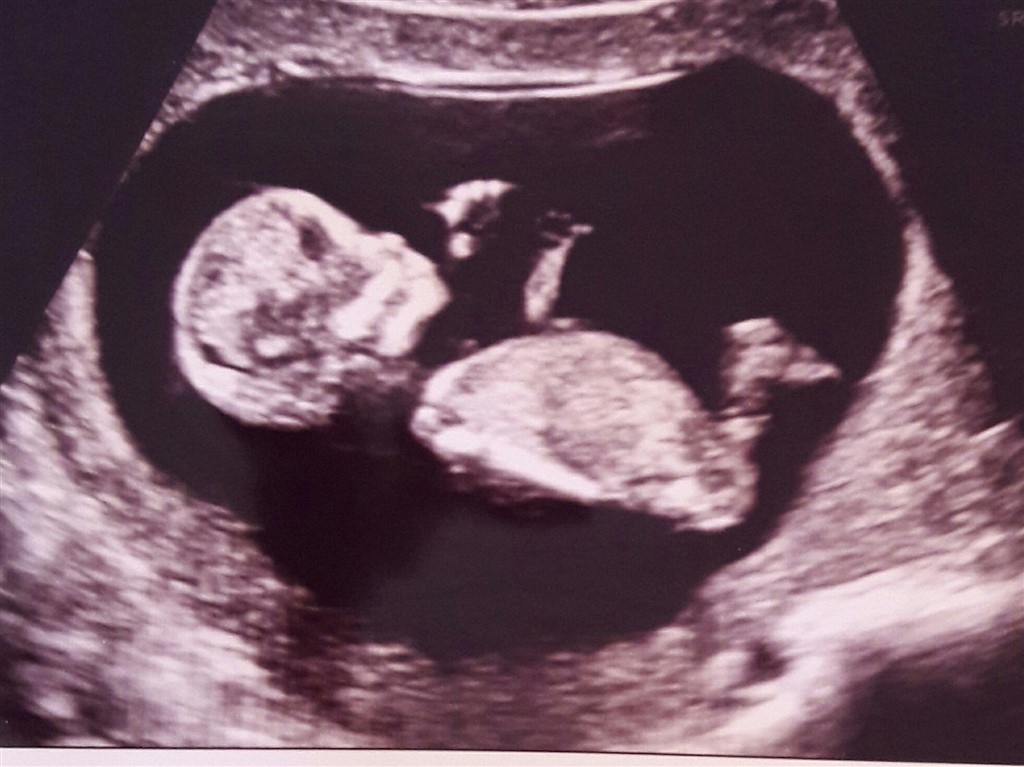

Billedet her er fra kønsscanning omkring 14+5 og er en pige. vi får det bekræftet ved misdannelsesscanningen, hvor vi ikke fortæller, at vi godt ved det i forvejen. Havde brug for dobbeltbekræftelse.

Men det er så svært.. tilmodighed er en dyd. Synes først det lignede lidt jeres, men nu bliver jeg alligevel i tvivl